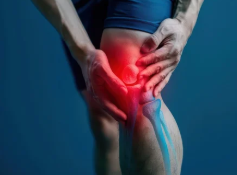

2. 오금 통증과 함께 나타나는 증상

✔ 무릎 뒤쪽 붓기 & 뻣뻣함 – 베이커 낭종, 관절염 가능성

✔ 통증이 걸을 때 심해짐 – 인대 손상 또는 좌골신경통 의심

✔ 무릎을 구부릴 때 찌릿한 느낌 – 반월상연골판 손상 가능성

✔ 다리가 저리고 감각이 둔해짐 – 신경 압박(허리 디스크, 좌골신경통) 가능성

✔ 무릎 뒤쪽에서 열감 & 붉은 기운 – 혈전 가능성(즉시 병원 방문 필요)

📌 즉, 오금 통증과 동반되는 증상을 통해 원인을 추측할 수 있으며, 혈관 문제라면 빠른 진료가 필요하다.